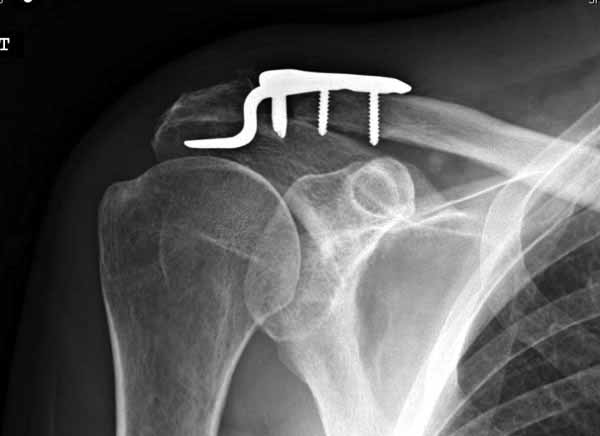

Re: ключичная пластинка

Отправитель: Серж 24 Июнь 2011, 13:43

foto 4

4.JPG

Замечание понял, спасибо и нормальные рентгенограммы, молодец!

Во вторых, это хорошо что нашли длинную пластину, я об этом писал "пластина короткая, не покрывает медиальный диафизарный фрагмент ключицы", и у нас не получилось, пластина не выдержала...